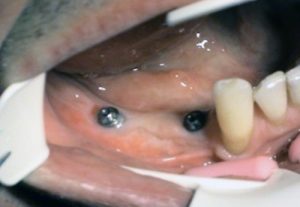

1. PHASE – implant insertion

2. PHASE – state before making immediate impressions